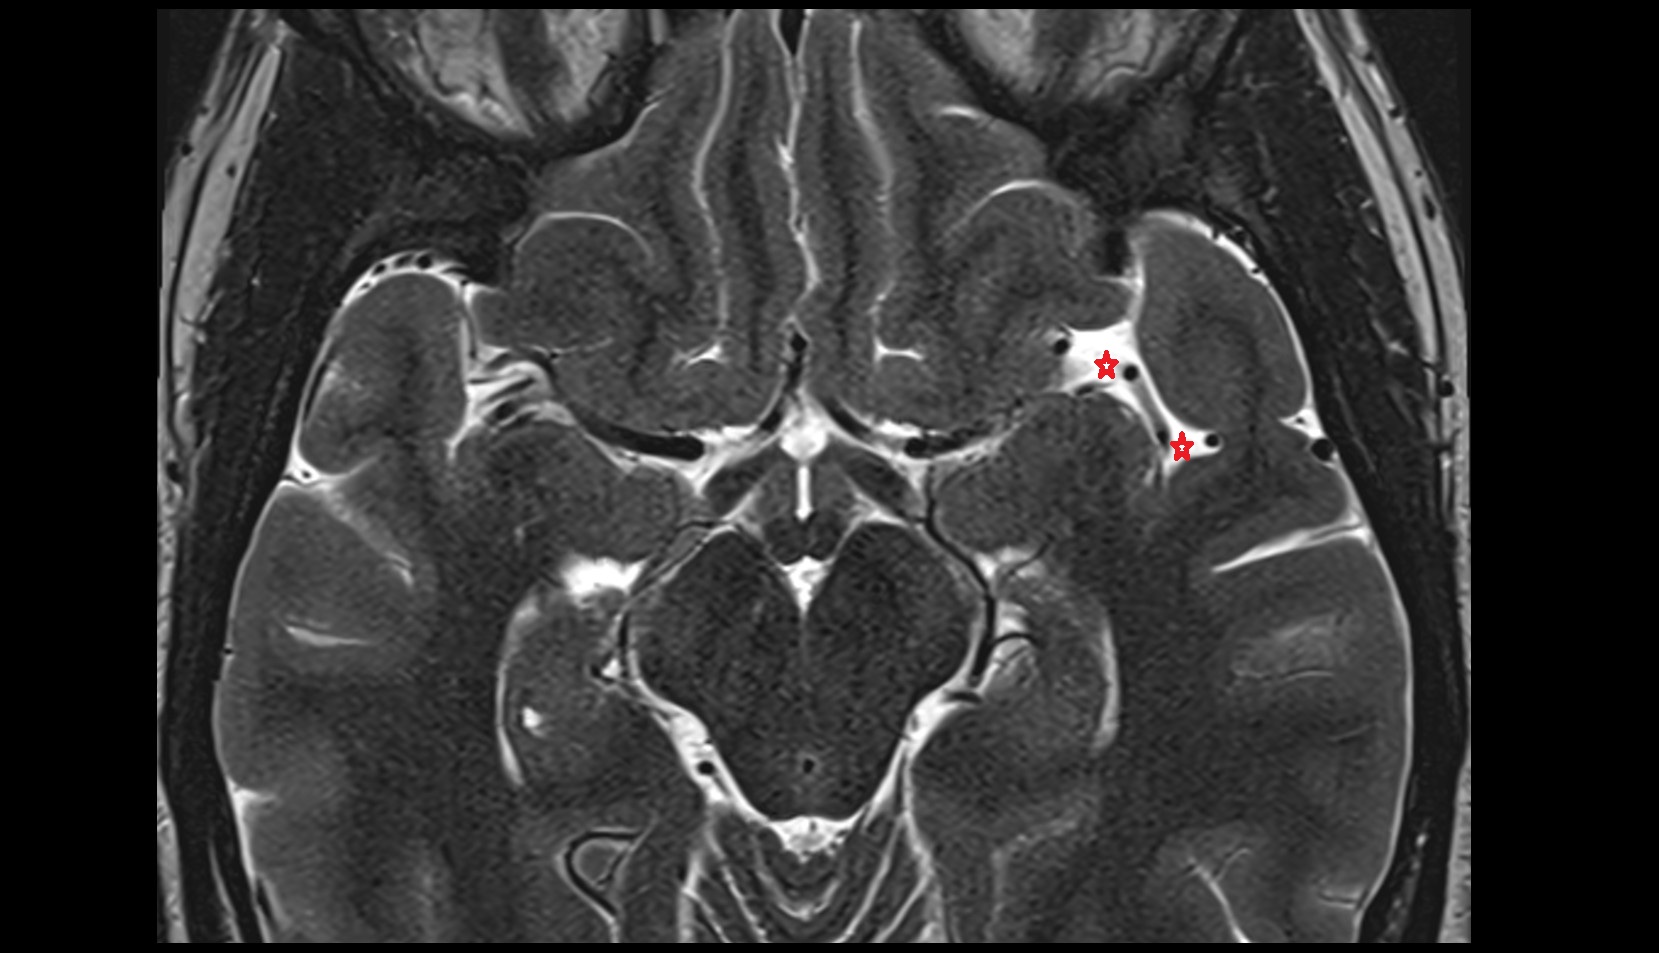

- Flocculus

- Cerebellar tonsil (H IX)